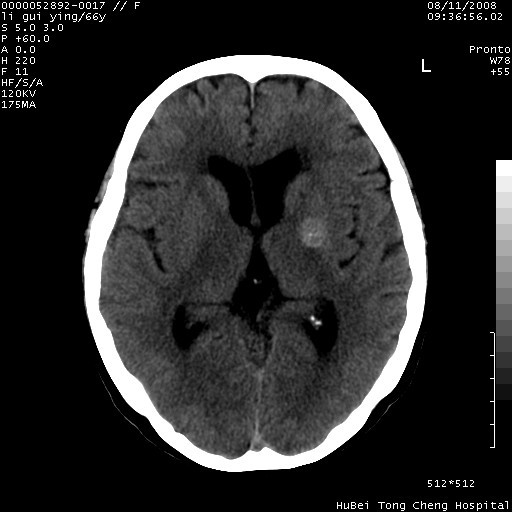

以下是引用sdzyy在2008-8-12 9:59:00的发言:[br]血管瘤可能性大

以下是引用代课学生在2008-8-12 9:48:00的发言:[br]考虑出血灶可能性大。

以下是引用yangyudong333在2008-8-12 12:22:00的发言:[br]1.病灶呈圆形[br]2.周围无水肿带[br]3.密度不均匀,内有点状钙化[br]4.无占位效应[br] 考虑良性占位性病变,血管瘤可能性大